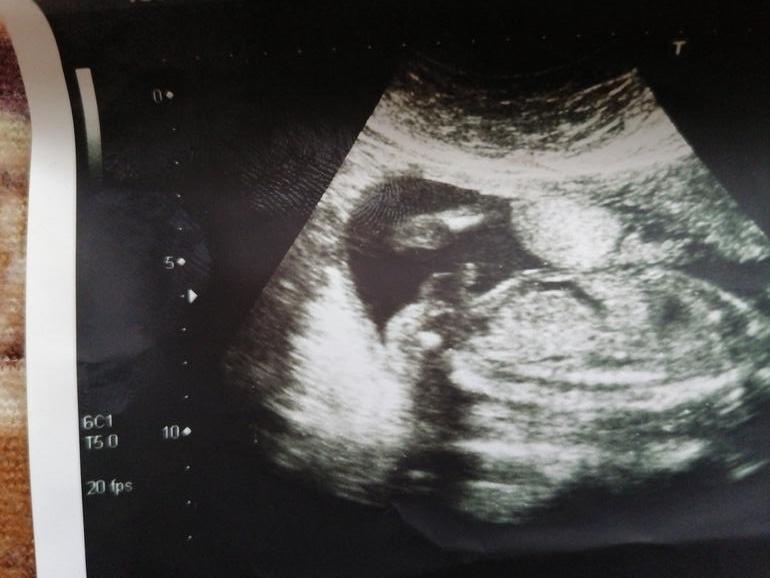

Узи. Всё равно надеюсь на девочку)))

Всё о нашей беременностиДевчонки привет. Идёт уже 25 неделя. Уже у меня 3 сынишки(11лет и двойняшки 1,7).беременность третья отличается от двух первых. Ем только сладости и молочку. Да и по ощущениям все другое. Имя не могу выбрать, хотя мальчикам быстро придумали.вообщем все называю малыша Бусинка))) При виде платиц и бантиков аж мандраж)))Конечно кто бы не родился, лиж бы здоровый, но так хочется принцессу в мою армию парней)))) Вот узи мне кажется там не писюн😂😂😂

А мне кажется девочка. У меня есть такое же фото с узи в 13 недель, и там такой орех, что точно не перепутать, там мальчик 😂

А у вас там все гладенько же☺️

Я лично вообще ничего не могу разобрать на фото))))😄 кто чё видит?)))😂😂😂 видно просто милый маленький малыш. Какая разница кто😍😍😍

Вот и я про то. Или нога или пуповина. Вообще родиться увидим)))) Главное чтобы здоровый и крепкий))))